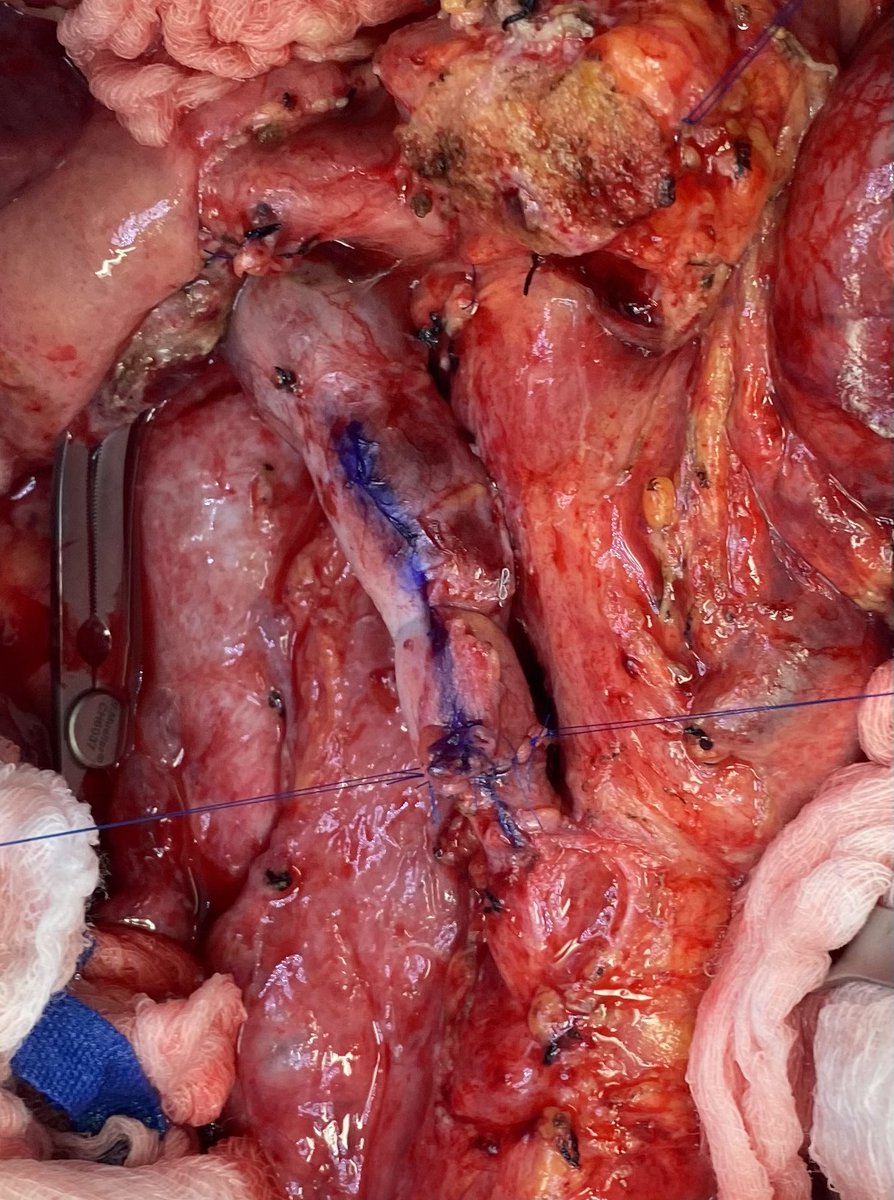

This week’s venous reconstructions covered the gamut. Thought an IJ interposition would be necessary for a 3.5cm resection of the PV/SMV confluence…amazing what is amenable to a primary anastomosis after liver mobilization and Cattell-Braasch. @AHPBA @SocSurgOnc @PancreasClub